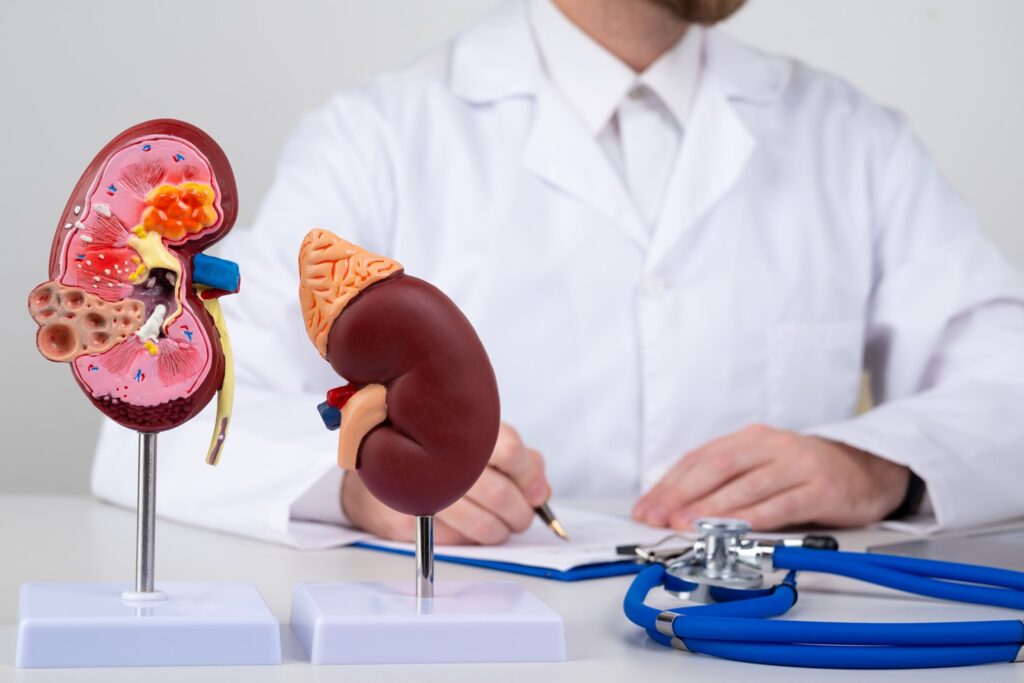

Know More About Renal Biopsy

Renal biopsy is a medical procedure in which a small piece of kidney tissue is removed for microscopic examination. It is usually performed to diagnose